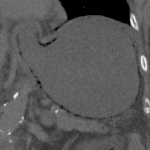

Age: 97

Sex: Male

Indication: Abdominal pain, hypotension

Sample ReportExtensive pneumatosis involving the stomach, small bowel, and large bowel with portal venous gas concerning for bowel ischemia. No pneumoperitoneum. Pneumatosis extends from the stomach into the lower thoracic esophagus.

Left upper pole renal neoplasm with likely metastatic lesions involving the right iliac wing, left pubic root and superior pubic ramus, and left inferior pubic ramus with associated pathologic fractures and periosteal reaction.

Right mesenteric mass, ill-defined para-aortic nodal tissue, and enlarged left inguinal node could represent additional sites of metastatic disease or could relate to a second primary neoplasm. Given the relative transition point in small bowel caliber near the right lower quadrant mesenteric mass, small bowel obstruction as an inciting factor for bowel ischemia is a consideration.